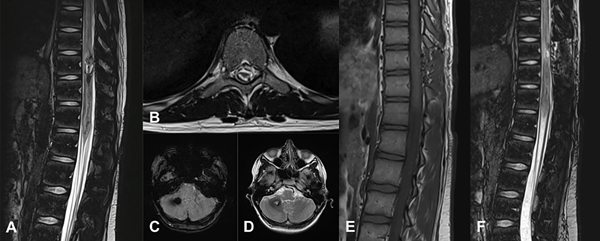

Figura 6. MC medular a nivel T10. Paciente masculino de 15 años que ingresa por paraplejía progresiva de varios días de evolución y compromiso de esfínteres. A) RM de columna dorsolumbar corte sagital T2-STIR que evidencia lesión heterogénea, compatible con MC. B) RM corte axial T2-STIR. C-D) RM de cerebro secuencias SWI y T2 que muestra otra lesión en hemisferio cerebeloso derecho. Por la severidad del cuadro clínico se realizó cirugía de urgencia. E-F) RM de columna dorsolumbar postquirúrgica, secuencias T1 y T2-STIR donde se observa el lecho quirúrgico libre de lesión. Se observa laminectomía del nivel T10. El paciente tuvo una recuperación parcial del foco neurológico. Actualmente en rehabilitación.

En nuestra serie presentamos un único caso de lesión espinal sintomática, con lesión intracraneal concomitante asintomática (ver Figura 6). El paciente se presentó con cuadro motor de más de 72 horas de evolución, llegando a la consulta con paraplejia, nivel sensitivo y alteraciones esfinterianas. Se instauró tratamiento de exéresis total de urgencia, en concordancia con la bibliografía. Se obtuvo una recuperación motora parcial, requiere de ayuda para las actividades de la vida cotidiana, sin recuperación de sensibilidad ni esfínteres.